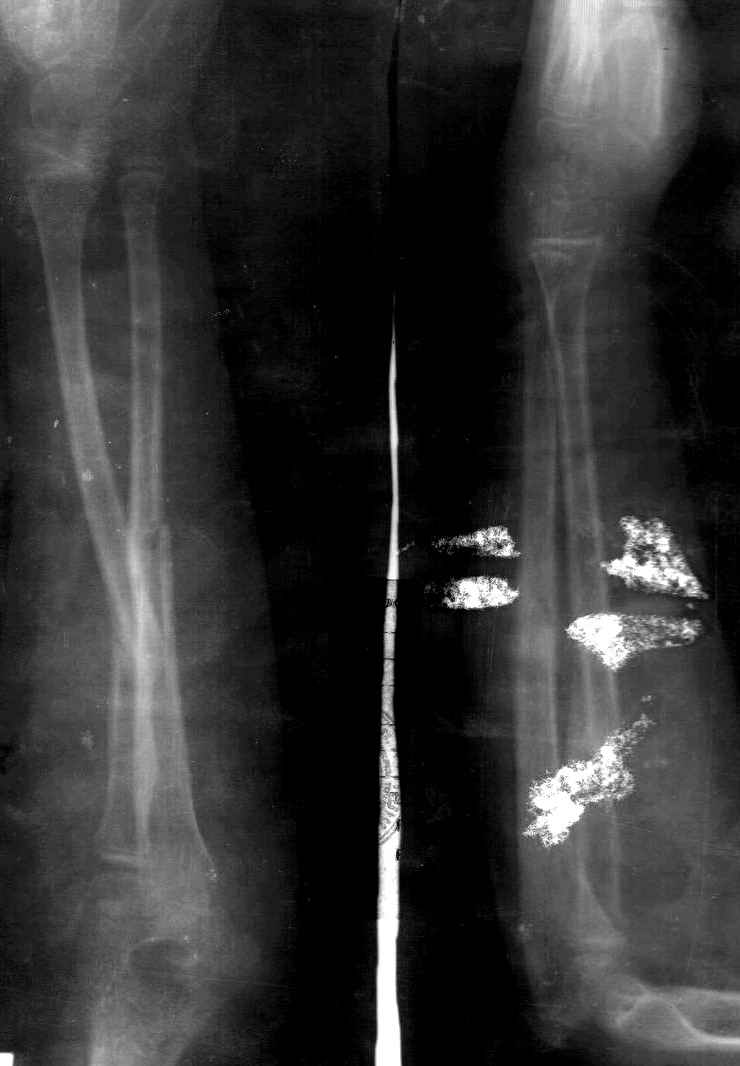

Снимок один сделан с супинацией, второй - оба предплечья в одинаково нейтральном положении. то есть по этим снимкам объем ротационных движений не оценить. Снимко в двух проекциях лучше и делать в среднем положении между пронацией и супинацией, то есть обе проекции в однм и том же положении, когда линия, проходящая через шиловидные отростки, идет в плоскости головки. Прошу прощения за усложнение простых вещей.

А для оценки ротации лучше сделать фото - дать пациенту зажать в кулаки одинаковые палочки (телескопы от апп. Илизарова идеальны), поставить... Впрочем, вот фото, чтобы все было понятно без слов. Локти к бокам пусть остаются прижатыми не только при супинации, но и при пронации.